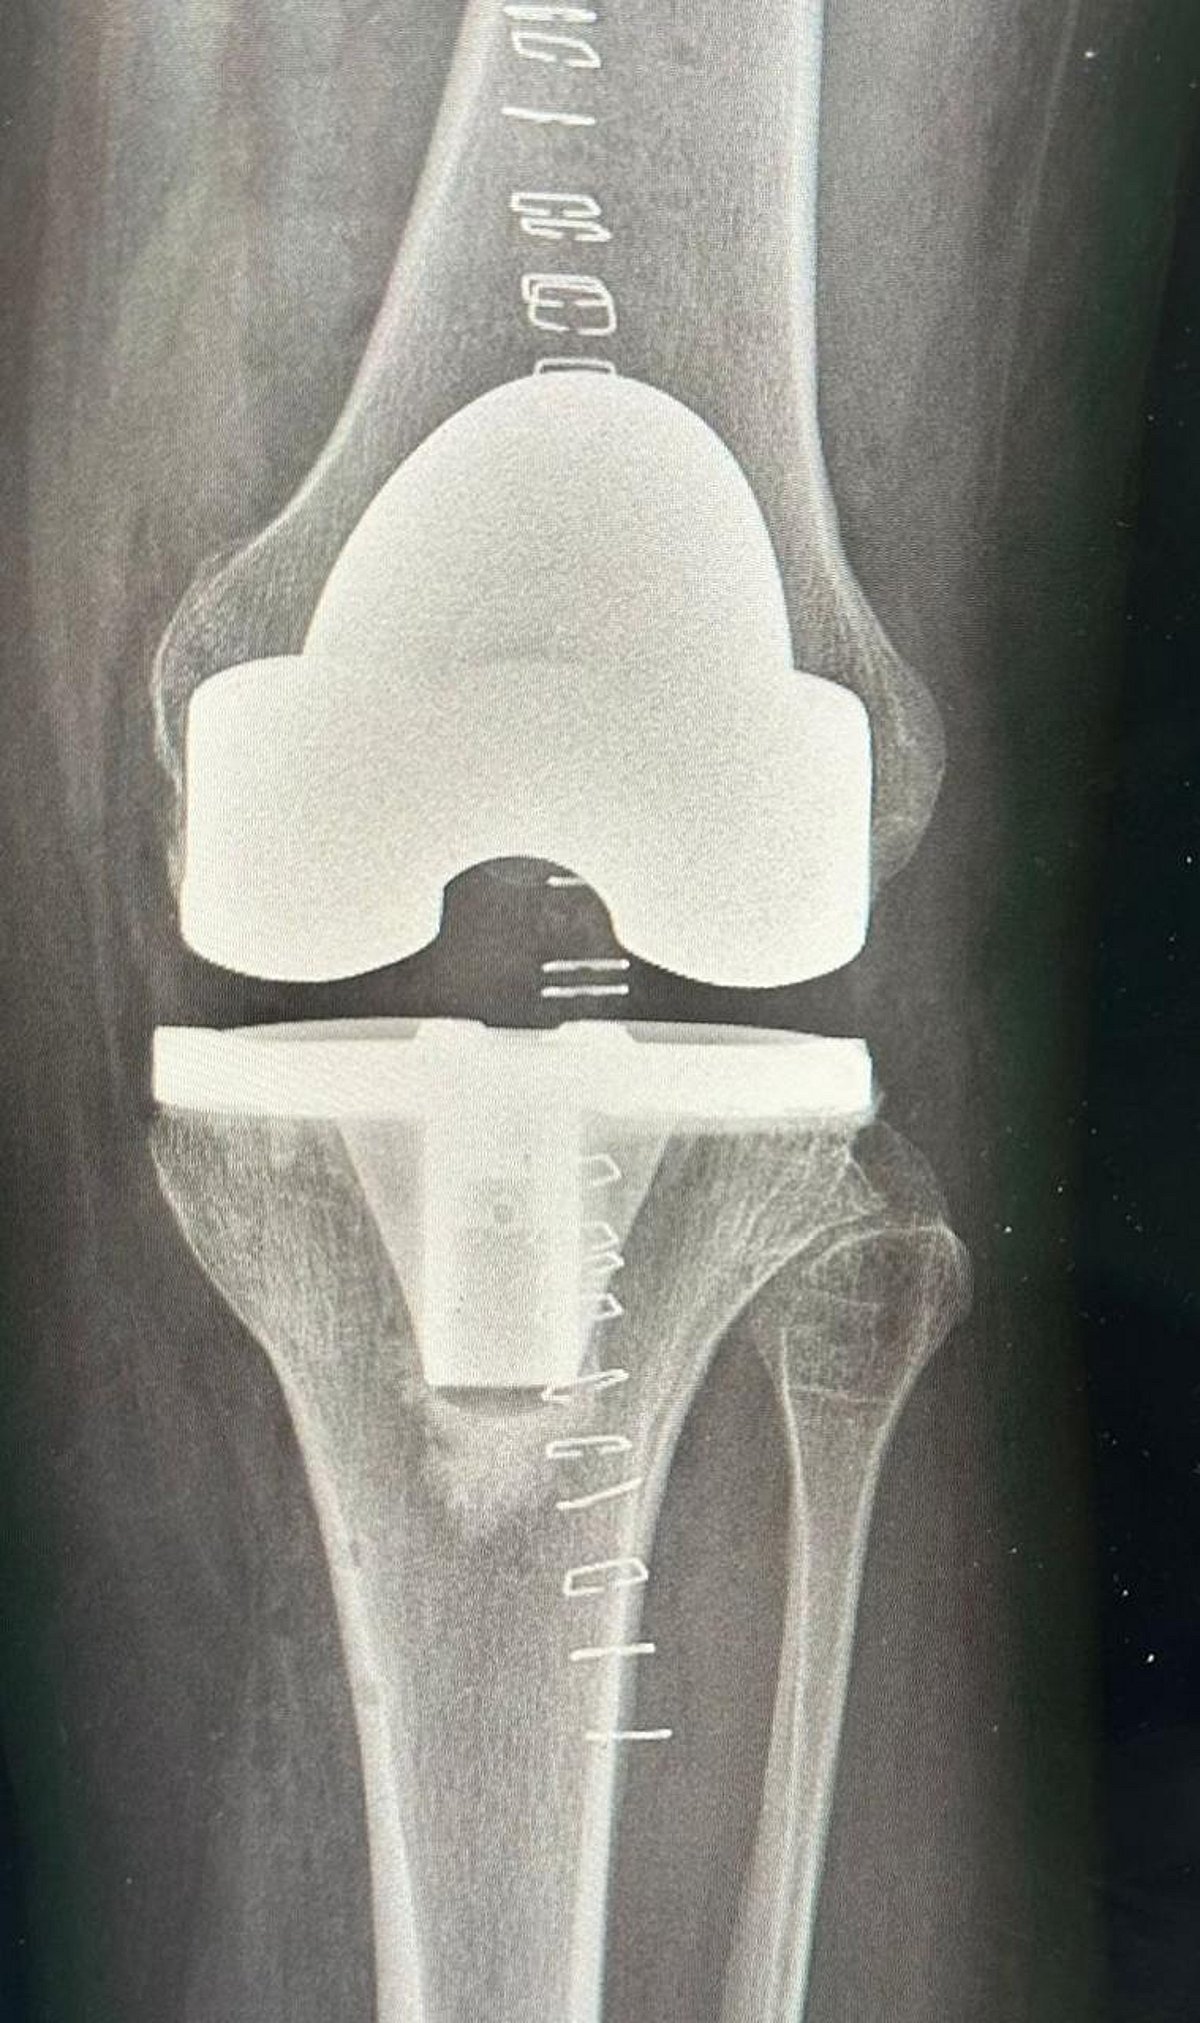

تمكن الفريق الطبي في مستشفى الدرعية، عضو تجمع الرياض الصحي الثالث، من إجراء عملية ناجحة لاستبدال مفصل الركبة اليسرى بتقنية الروبوت، بقيادة الطبيب الزائر د. فوزي الجاسر، بروفيسور جراحة العظام واستشاري تبديل المفاصل والأورام.